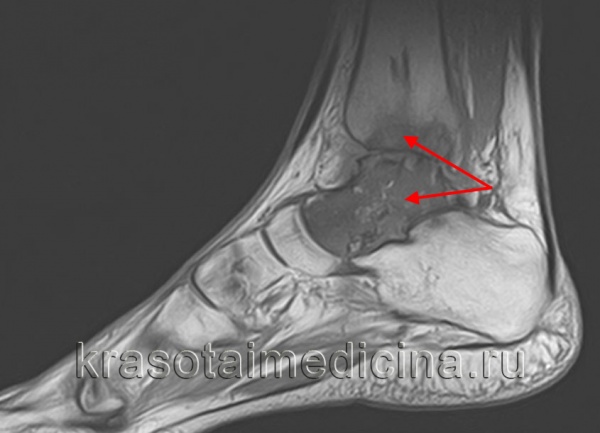

МРТ стопы. Остеомиелит таранной и большеберцовой кости с наличием обширной зоны деструкции костной ткани.